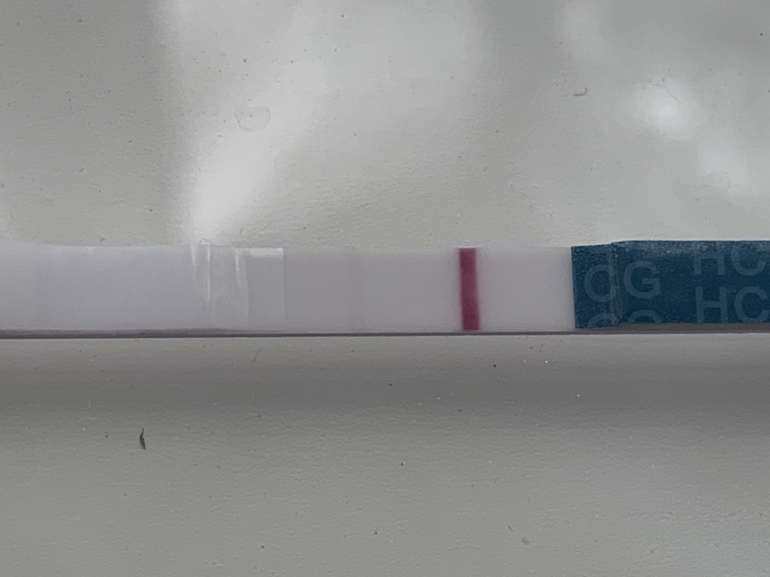

Всем привет! Сегодня 10 ДПО. Замочила тест в обед. Что думаете это ОНО самое 🥺 или реагент 🙁? Внизу фото без обработки и с фильтром. Тест эвиплан (шёл в комплекте с тестами на овуляцию).

А это уже когда тест высох!!

Полоска то хорошая прям, явно не реагент. Да и на эви не я, не знакомые никогда не видели реагент,. Поздравляю 💐💐💐

Оно оно ! Ярчайте

Оно.у меня такая на первом тесте была, тут написали что реагент. Реагенту уже два месяца 😂

Полосочки конечно!